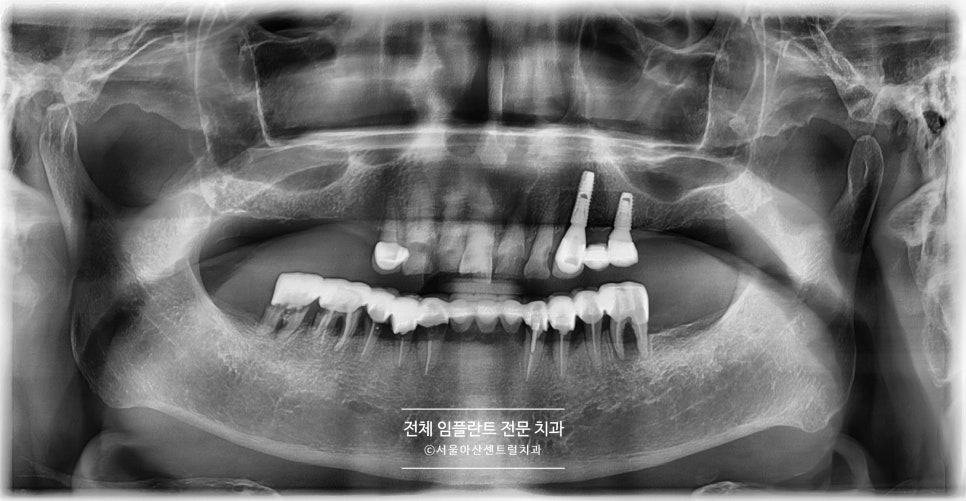

우선 위 파노라마 사진의 상태일 경우,

살릴 수있는 치아에는 브릿지 치료가 진행될 수 있습니다.

그 이후 발치가 필요한 치아는 모두 발치하고,

임플란트 식립이 필요하게 되는데요.

보통 성남치과에서 임플란트 식립 시

네비게이션 임플란트를 많이 진행하시지만

당일 식립 그리고 골이식까지 필요한 경우에는

오히려 부명확해질 수 있어,

수면치료를 통해 전체 임플란트를

받는게 좋을 수 있습니다.